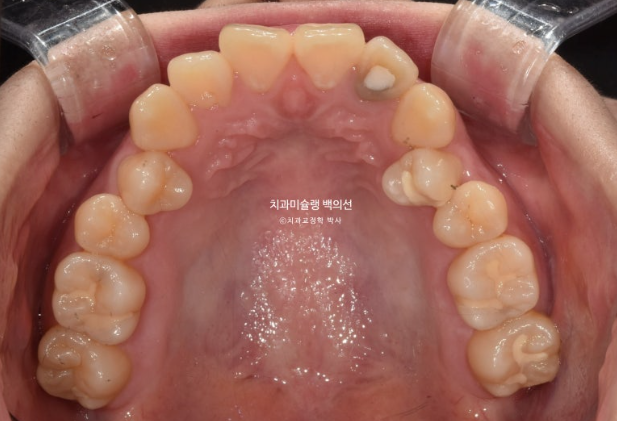

교합은 거꾸로 물리는 어금니 반대교합도 있고, 뜨는 부분도 있고 앞니 하나는 신경치료 후 변색이 되어 있습니다.

작은어금니가 입천장으로 들어가 있어 반대교합 상태였습니다.

첫 세트 장치는 30개가 나왔으며 위 앞니 뿐만 아니라 어금니까지 전체치열을 후방이동하며 함입시키는 계획입니다.

어금니 교합은 좋습니다.

배열도 대부분 완료되었습니다.